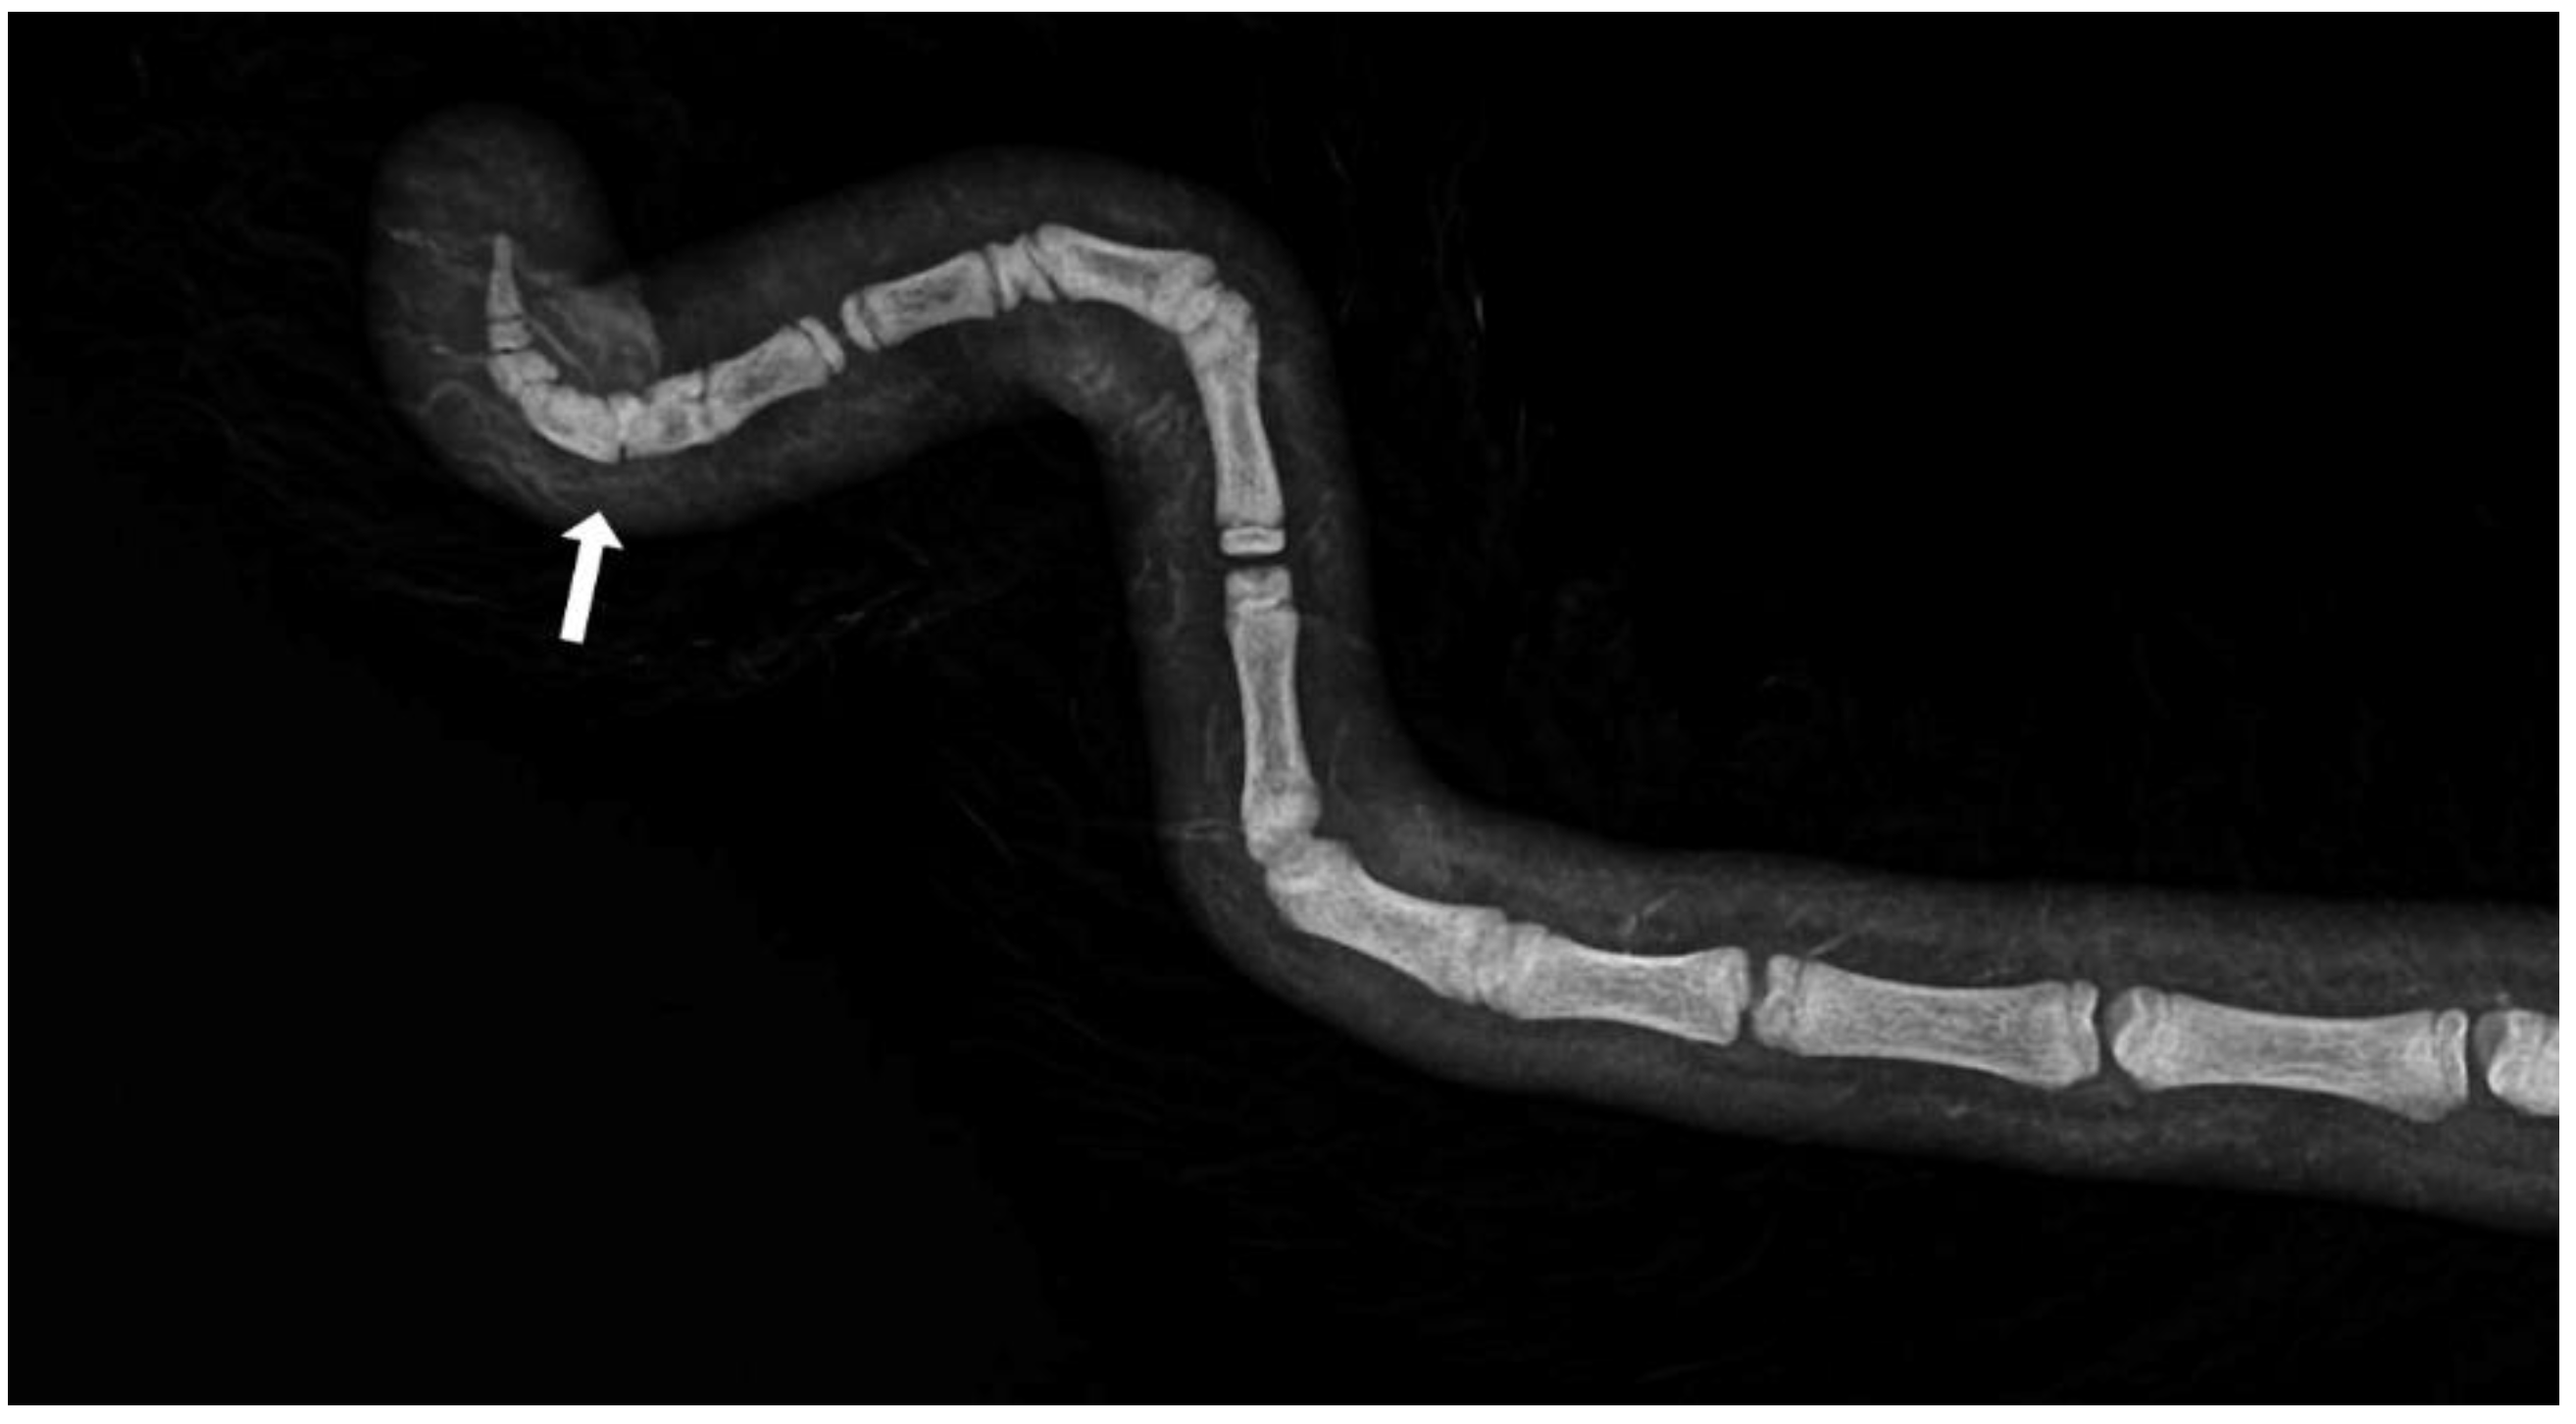

Axial deviation was defined as any manually irreparable deviation of the tail from the medians (Figure 1). A block vertebra was considered present if the vertebral boundaries of adjacent vertebrae were not clearly visible or were completely fused (Figure 2). Wedge-shaped bony structures present between two vertebrae were recorded as wedged vertebrae (Figure 3). A fracture was noted in any event where a vertebra demonstrated an interruption of bone structure (Figure 4).

Figure 4. Section of an X-ray of a lamb’s tail with fractured vertebrae.

The mean number of tail vertebrae in the Merinoland sheep population was 20.4 (±1.6) vertebrae. The mean tail length at 14 weeks of life was 41.6 cm (±4.3 cm) and mean tail circumference measured at the same time was 13.15 cm (±1.3 cm). In 33 animals (15.28%), an axial deviation of the tail spine was detected. Radiographic examination revealed various spinal lesions, such as fractures (Figure 4), wedged vertebrae (Figure 3), and block vertebrae (Figure 2). In the caudal spine, at least one block vertebra was found in 28 animals (12.96%) and at least one wedged vertebra was detected in 18 animals (8.33%). A total of 59 animals (27.51%) exhibited at least one vertebral fracture within the caudal spine. In 51 of these 59 animals (86.4%), the fracture localisation was limited to the caudal third of the tail. Six animals (10.2%) had fractures in the middle third of the tail and two animals (3.4%) had vertebral fractures in both the middle and caudal third of the tail (Table 1).

Since the lambs examined in the present study were not radiographically examined until 14 weeks of age, it was not possible to assess which abnormalities were congenital and which developed in the course of rearing. It can be assumed that fractures of the vertebrae arise from trauma, as per previous description of tread injuries in the tail area of undocked animals [1]. Whether these fractures result in ankyloses in the form of block vertebrae cannot be assessed at present due to the lack of radiographs during the development phase. As such, future imaging studies of lambs during the first weeks of life are necessary to further develop our understanding of the origin of lamb tail malformations.

In principle, block vertebrae are formed by the fusion of two adjacent vertebrae [27,28]. This fusion, which bridges the intervertebral gap, can lead to an axial deviation of the tail in the form of a kink [26,29]. However, other factors may also result in a kinked tail. In this study, for example, in addition to block vertebrae, associated separations in the intervertebral fissure and vertebral fractures were observed in connection with an axial deviation in the caudal spine. This complicates the phenotypic assessment of the caudal spine to the extent that no precise statement can be made about the presence of malformations without radiographic examination. This, in turn, may lead to axis deviations being incorrectly attributed to acquired malformations (such as vertebral fractures or cohesive separations), and a malformation being disregarded as the cause.